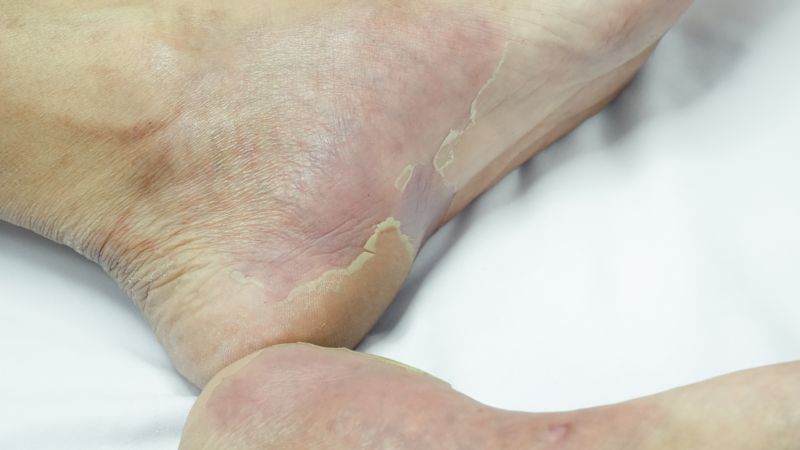

Bệnh nhân nam H.T. (sinh năm 1975) đến khám tại Khoa Da liễu – Miễn dịch dị ứng, Bệnh viện Thống Nhất trong tình trạng xuất hiện các chấm ban đỏ, xuất huyết nhỏ ở hai bàn chân, kèm đau nhức nhẹ khi đi lại. Người bệnh được chỉ định sinh thiết da, làm giải phẫu bệnh để xác định chẩn đoán và tầm soát nguyên nhân, đồng thời tư vấn bệnh nhân nhập viện điều trị. Tuy nhiên, bệnh nhân xin sắp xếp công việc sẽ nhập viện điều trị sau.

Theo BSNT.CK1 Châu Quốc Khánh, đây là biểu hiện sớm của hội chứng viêm mạch – tình trạng viêm và tổn thương thành mạch máu liên quan đến cơ chế miễn dịch, dễ bị nhầm với các bệnh da thông thường ở giai đoạn đầu.

Nhờ điều trị đúng nguyên nhân nền, sau 1 ngày tình trạng xuất huyết tiêu hóa cải thiện nhanh; sau năm ngày, các thương tổn da giảm rõ rệt, đau nhức thuyên giảm, khả năng vận động phục hồi tốt, sức khỏe người bệnh cải thiện đáng kể.